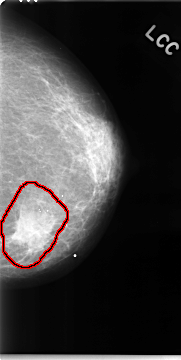

C_0050_1.LEFT_CC

FILE: C_0050_1.LEFT_CC.OVERLAY

TOTAL_ABNORMALITIES 1

ABNORMALITY 1

LESION_TYPE MASS SHAPE IRREGULAR MARGINS SPICULATED

ASSESSMENT 5

SUBTLETY 5

PATHOLOGY MALIGNANT

TOTAL_OUTLINES 1

BOUNDARY